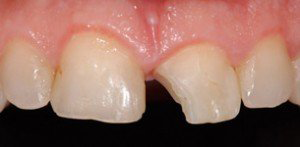

Cas 1 : 1 incisive latérale et 1 canine - 2 séances de 60 minutes la même journée